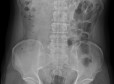

엑스레이에선 형체가 하나도 망가지지 않은 길이 십여센치의 쉐이빙 폼이 찍혀 나왔다. 윗 부분의 분사구와, 아래의 반구 모양, 긴 몸통이 선명하게 의료용 엑스레이 화면에 떠 있었다. 그 모양은 너무 온전해, 마치 누가 그 통을 손에 들고 감마선을 잘 겨냥해 찍어 놓은 것 같았다. 그걸 들고 있는 것은 그의 직장直腸이었지만 말이다.

"여기, 엑스레이 보이시죠? 이거, 겹쳐서 찍힌 거 아닙니다. 배 안에 들어있는 겁니다."